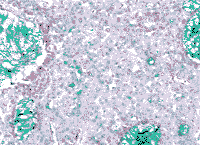

图4 粘蛋白性癌。大量的细胞内和细胞外粘蛋白为奥辛绿染色所证实(原大×200)